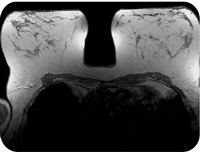

MRI

The Magnetic Resonance Imaging (MRI) scan is a procedure in the medical world used to provide a detailed picture of the organs and tissues, for head to toe examination. We provide Neuro , Ortho , Body Angio ,Cardiac, Breast, Oncology, Pediatric Patients with intercom & automatic & freely programmable voice command for breath hold examinations. The equipment makes use of radio waves and strong magnetic force to produce a detailed image of the organ and tissue of the body, In a most comfortable & smart Seimens 1.5T Machine We provide MRI in Lifecare Scan & Research Centre Durg / Bhilai at a very affordable cost.